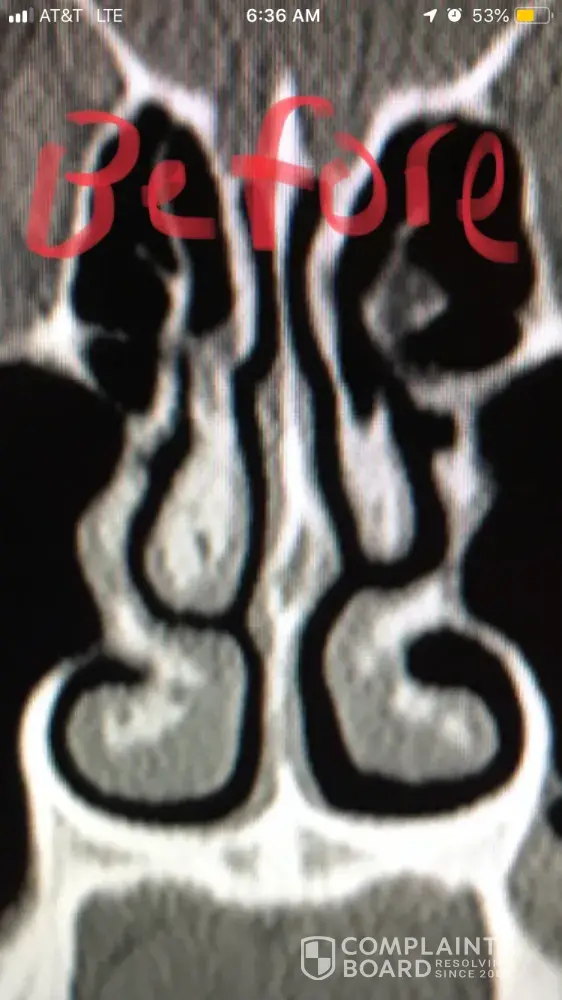

For people reading this, I have included x-ray images of the inside of my nose, before and after my surgery with him. As you can see from these images, my nasal airway was equally open on both sides, before surgery, and the septoplasty didn't need to be done. By performing it, he severely narrowed the right side of my nasal airway.

Dr Raviv performed two surgeries on me: endoscopic sinus surgery (where they widen the sinus passages), and septoplasty (where they straighten the septum). The septoplasty, however was completely unnecessary, and severely narrowed the right side of my nasal airway. For people reading this, I have included x-ray images of my sinuses, before and after my surgery with Dr. Raviv. As you can see from the surgery, my airway was much more open, and equal on both sides, before my surgery with him.